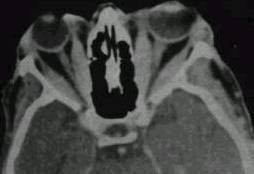

What type of image is it? CT scans or MRI scans (T1 or T2

weighted)

Which plane the image is in? axial, sagittal or coronal.

extraocular muscle enlargement (the main differetial

diagnosis include: thyroid eye disease if tendon is not involved or myositis

if the tendon is involved; other possibilities include neoplasm either

primary or secondary)?

space occupying lesion in the orbit: lacrimal

fossa (lacrimal gland tumour)? intraconal lesion (optic glioma, capillary

haemangioma or optic nerve meningioma)? diffuse lesion (lymphoma, metastatic

tumour or acute infection or inflammation)? dilated superior ophthalmic

vein (carotid-cavernous fistula)?